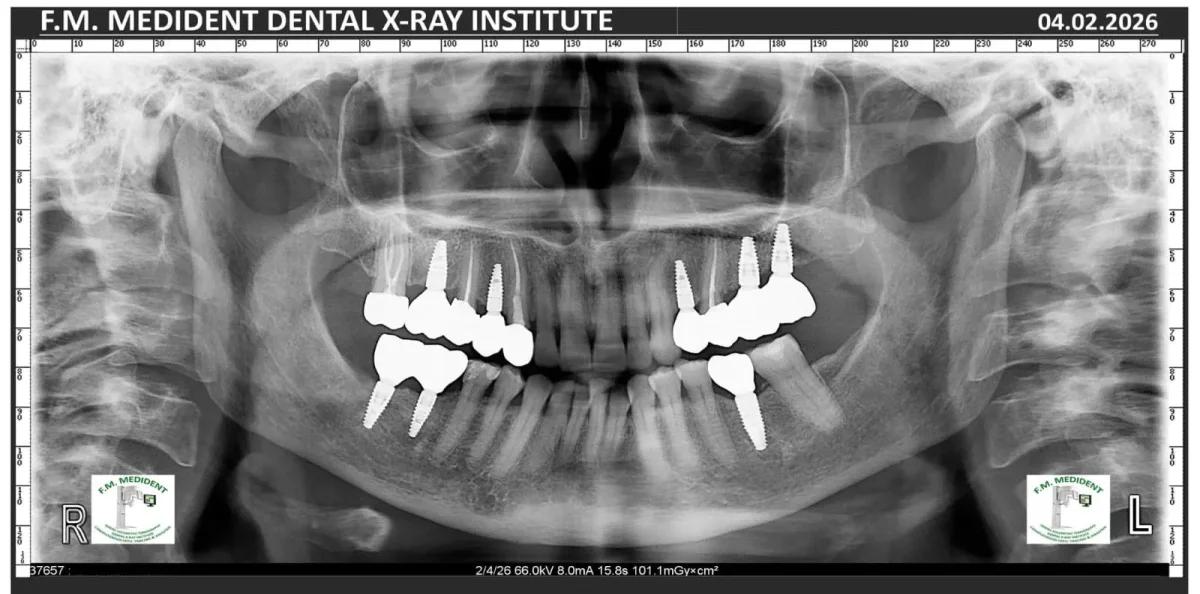

Cazuri reale înainte și după, din tratamente realizate în clinică.

Înainte

DupăExemple reale din cazuri tratate în clinică.